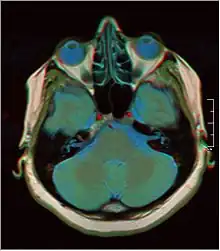

![]() Cross-sectional T1-weighted MRI of a healthy human brain acquired with an ultra high-field MR of 7 Tesla field strength | |

Magnetic resonance imaging of the brain uses magnetic resonance imaging (MRI) to produce high-quality two- or three-dimensional images of the brain, brainstem, and cerebellum without ionizing radiation (X-rays) or radioactive tracers.